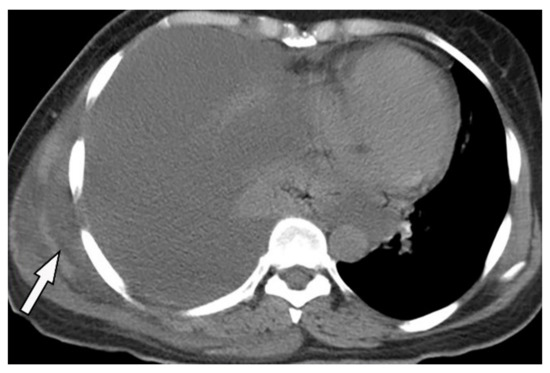

11.3. Mesothelioma

Malignant mesothelioma is the most common primary tumor of the pleura, which is related to prior asbestos exposure with a relatively poor prognosis [56].

Multidetector CT effectively reveals the primary tumoral extension, lymphadenopathy, and extrathoracic metastasis (Figure 27 and Figure 28) [56]. Another CT finding is circumferential pleural thickening (most common finding) with extension along the fissures. Large or punctate osseous or cartilaginous differentiation is more in favor of malignant mesothelioma rather than linear calcification that usually occurs within asbestosis plaques. Dynamic contrast-enhanced computed tomography (DCE CT) enables measuring intratumoral capillary permeability and blood flow, which are beneficial in evaluating treatment response [56,57,58].

Figure 27.

A 67-year-old man with dyspnea and chest pain. Contrast-enhanced CT in axial (a) and coronal (b) planes demonstrate left-sided localized enhancing pleural mass (arrow) with internal areas of necrosis that extend to the posteromedial aspect of the chest wall. Involvement of diaphragmatic pleura and elevation of left hemidiaphragm are also identified.

Figure 28.

A 70-year-old man with dyspnea. The non-contrast CT in the axial plane demonstrates right-sided large pleural effusion, near complete collapse of the right lung (a) after the chest tube insertion; thick circumferential nodular pleural thickening of parietal pleura was shown (arrow) (b). Contrast-enhanced CT of the upper abdomen shows the extension of mesothelioma through the abdominal cavity and wall with indentation over adjacent liver parenchyma (arrow) (c).

MR imaging and 18F-FDG PET/CT are useful in further evaluation of chest wall, diaphragm, and mediastinal invasion [56,57,58,59]. Malignant mesothelioma appears as unilateral hyperintense pleural effusion and pleural thickening with iso to slight hyperintensity to chest wall muscles on T1-weighted and moderate hyperintensity on T2-weighted images. Post-contrast enhancement is expected (Table 3). It is believed that higher metabolic activity on 18F-FDG PET/CT is associated with poor prognosis and shorter survival time [25,56,57,58].